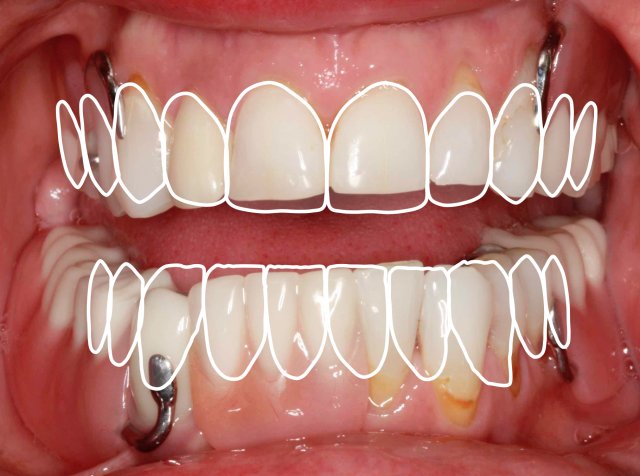

Partially edentulous — missing posterior teeth

A restorative treatment plan is identified for the patient maintaining the ability to select a path that makes sense whether teeth are removed or the remaining teeth are maintained. The outlines of the desired position of the teeth are helpful in identifying the challenges or compromises that are critical in the decision-making process in terms of how to proceed.

A sectional impression technique for this patient allows the opportunity to focus on the edentulous areas before capturing the remaining natural teeth. An accurate recording of the soft tissue and associated landmarks provides information helpful for the variety of treatment options that exist for this patient. Specifically, it’s helpful to know the thickness of the soft tissues relative to the supporting alveolar bone when creating a surgical guide in conjunction with a CBCT image for the placement and, in particular, the depth of the dental implants. When the goal is to transition a patient into a situation where all of the natural teeth are to be removed, the edentulous areas are the only consistent reference points.